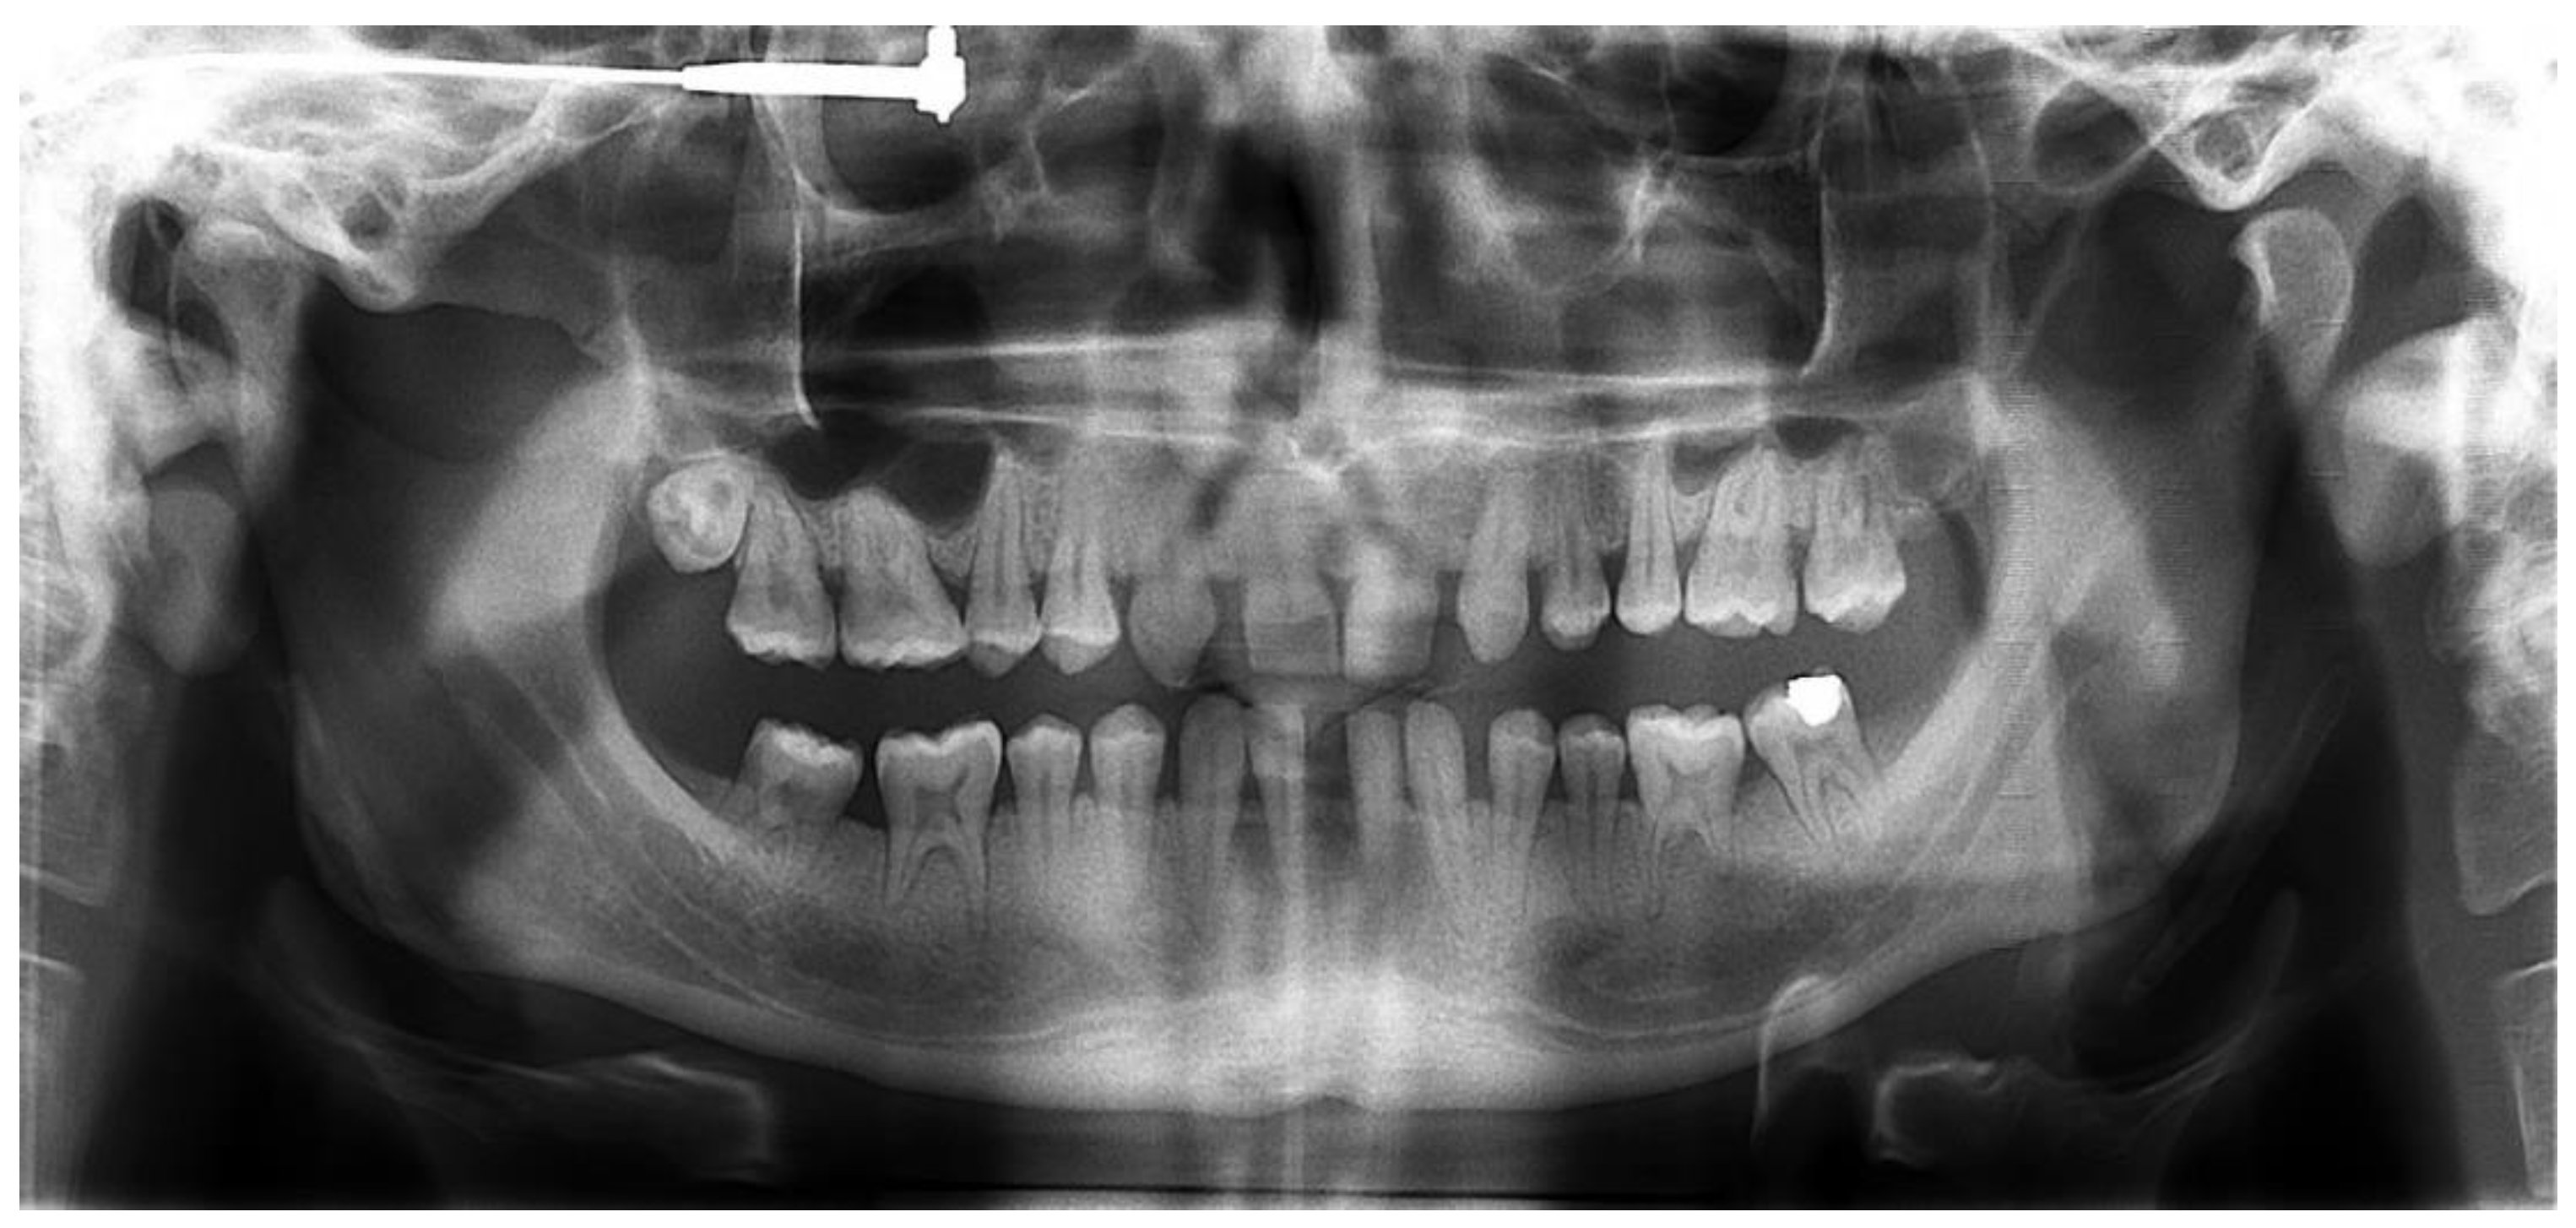

First, alginate impressions were made to obtain diagnostic casts. These casts were mounted in an articulator in order to analyze the case. Face photos and intraoral views were taken and are presented in Figure 1 and Figure 2. The orthopantomogram shown in Figure 3 was realized.

Figure 3.

Orthopantomogram of the patient’s initial dental condition in February 2021.

The radiological examination revealed voluminous dental pulps, apical root resorptions on the lower molars and the absence of the upper left third molar and the two lower third molars.